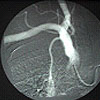

Carotid angiogram

with stenosis |